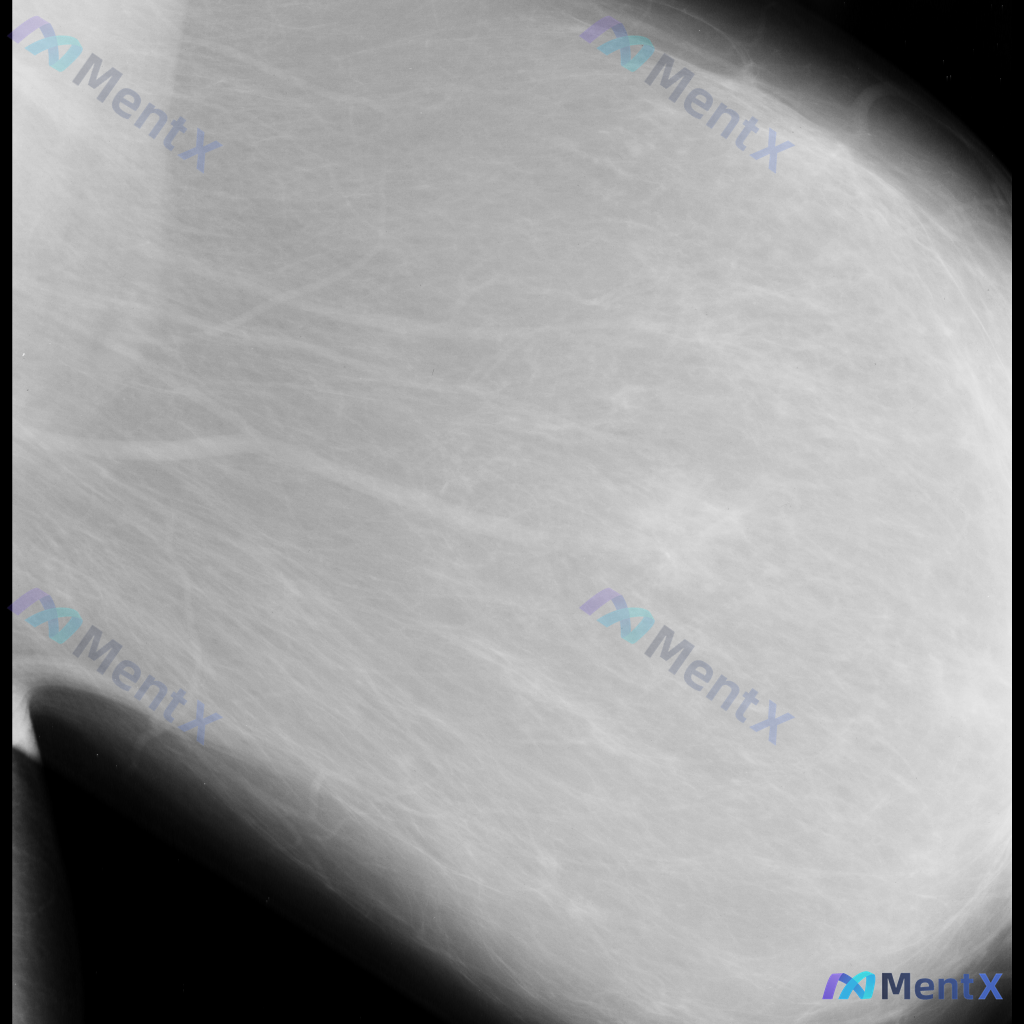

整理到一份乳腺钼靶的影像资料,先和大家讨论一下读片思路。 基本影像信息 - 图像类型:单张乳腺钼靶侧位片(具体投照体位未明确,无对侧对比) - 乳腺构成:不均匀致密型(ACR C型),腺体密度较高 目前可见的影像表现 - 图像中部偏外侧的纤维腺体组织结构走行略显紊乱,但不足以诊断为明确的结构扭曲 -...

整理到一份单侧乳腺钼靶MLO位的影像资料,想和大家讨论一下初步判断思路。 影像基本情况 - 投照位置:单侧乳腺MLO位 - 主要表现:乳腺组织不均匀致密,ACR BI-RADS c类;在致密的腺体背景下,可见部分区域的致密影,但边界比较模糊,暂不能明确界定为独立肿块。 目前只有这一个位置的影像资料,...